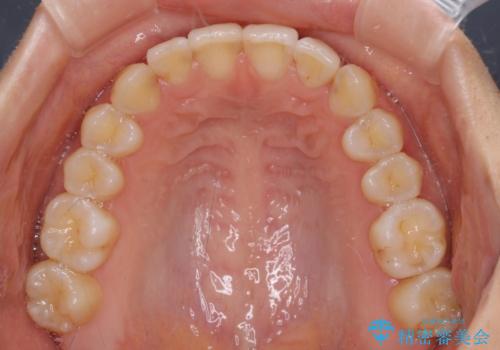

- 前歯の叢生と口元の閉じにくさを気にして来院された患者様です。

奥歯の咬み合わせを見ると、上顎が下顎に対して相対的に前方にありました。

口元の閉じにくさを改善するためには、上顎臼歯を後方に移動させた咬み合わせにする必要があります。

インビザライン単体で改善することも可能ですが、達成する可能性が高くないため、カリエールディスタライザーという補助装置を併用して、より確実性を上げることとしました。

奥歯の咬み合わせを改善しながら、並行してインビザラインで歯列を整えることとしました。

カリエールディスタライザーを併用したことで、確実かつ短期間で治療を終えることができました。